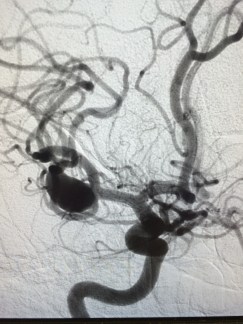

- Brain aneurysms are found only with special tests that look at the blood vessels in the brain called angiography.

- Non-invasive angiography include CT angiography and MR angiography

Best form of angiography is a conventional catheter-based diagnostic cerebral angiogram.

- This is an invasive test similar to a heart catheterization that uses fluoroscopy and contrast dye to provide a map of the blood vessels in the brain

- The quality and resolution of the images obtained are less than 1mm.